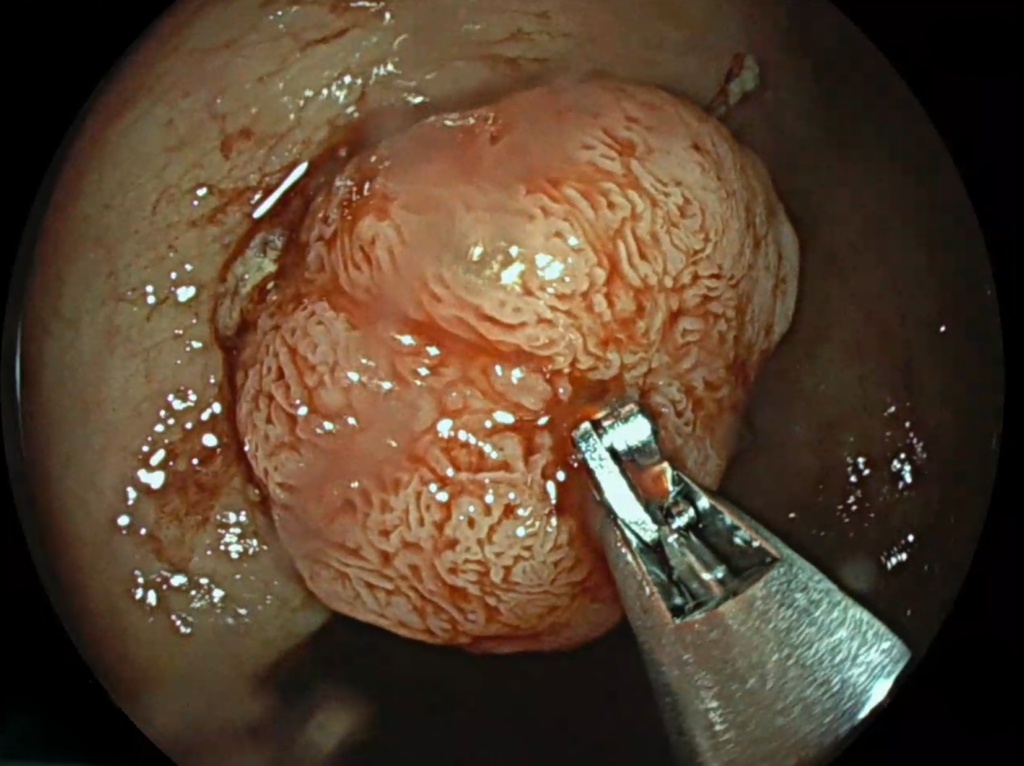

Prin monitorizarea constantă cardiavasculară, dr. Carmen Roxana Ionașcu-Fometescu, medic primar cardiologie, a observat semnele unei anemii feriprive și a solicitat o evaluare gastroenterologică. Investigațiile efectuate de dr. David Marica, specialist gastroenterolog au dus la diagnosticul de cancer colonic, ceea ce a impus o intervenție chirurgicală.

Inițial, evoluția postoperatorie a fost favorabilă. Totuși, pacientul a dezvoltat o hemoragie digestivă inferioară, gestionată prompt prin hemostază endoscopică de urgență de către dr. David Marica, în contextual nevoii constante de hemodializă.